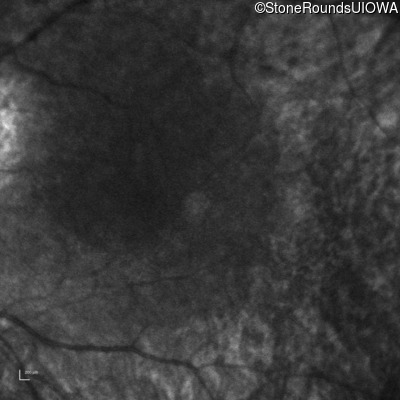

Infrared Fundus Photograph - Right -

No Light Perception

Infrared Fundus Photograph - Left -